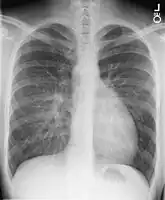

Chest X-ray: On chest X-ray (CXR), transposition of the great vessels typically shows a cardio-mediastinal silhouette appearing as an "egg on a string ", in which the enlarged heart represents an egg on its side and the narrowed, atrophic thymus of the superior mediastinum represents the string.[9]

X-ray showing characteristic finding in case of transposition of the great vessels which is called egg on side sign